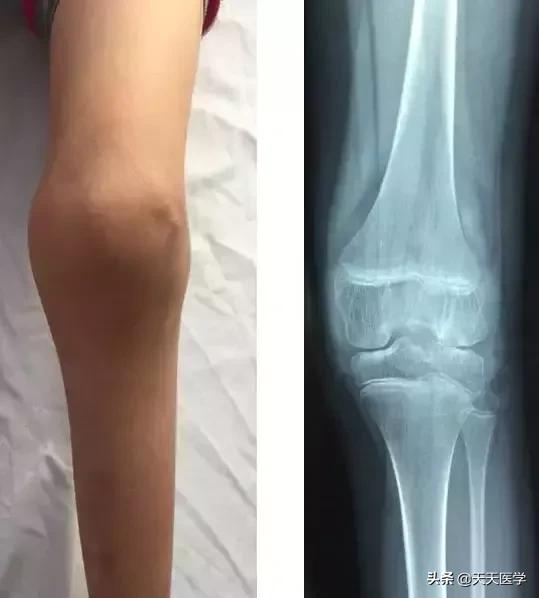

2.关节积血: 是血友病A患者常见的临床表现,常发生在创伤/行走过久/运动之后引起滑膜出血,多见于膝关节,其次为踝、髋、肘、肩、腕关节等处。关节出血可以分为三期:

(1)急性期:关节腔内及关节周围组织出血,导致关节局部发热、红肿、疼痛。继之肌肉痉挛、活动受限,关节多处于屈曲位置。

(3)后期:关节纤维化/关节强硬、畸形、肌肉萎缩、骨质破坏、关节挛缩导致功能丧失。膝关节反复出血,常引起膝屈曲,外翻、腓骨半脱位,形成特征性的血友病步伐。